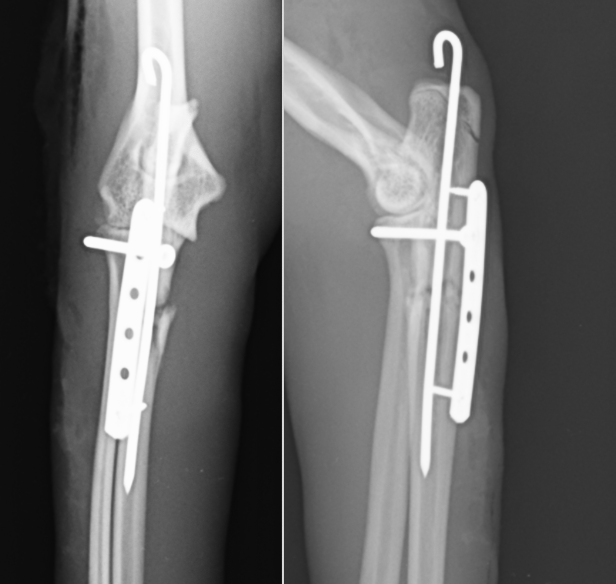

手術ではまず①尺骨の骨折を整復します。髄内ピンと呼ばれるものを打ち込み、ある程度骨折片同士を合わせたら、プレートを設置します。そうすることで骨片の回転を予防でき、腕を曲げ伸ばししたときに発生するひっぱり応力に抵抗することができます。

骨折が整復できたら、②橈骨の脱臼を整復します。輪状靭帯が切れてしまっているため、尺骨から頭骨に向けてスクリューを打ち込むことで再建が可能です。最後に海面骨移植を行い終了としました。

術後のレントゲンです。